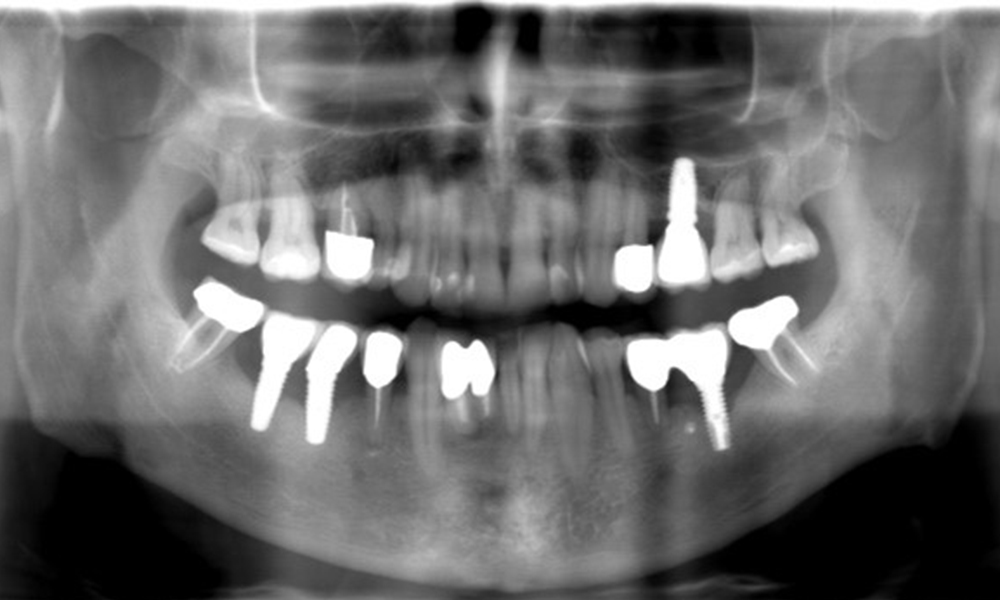

A 52-year-old patient presents at a preventive care session. The patient has no systemic disease and is not taking any medication. He has had various dental treatments and also has two active carious lesions. In addition, the patient has four implants (2nd, 3rd and 4th quadrants). He is revealed to have early periodontal disease (stage IV, grade B). His periodontal condition is stable; a probing depth of Probing depths (ST) of 5 mm is only evident at the implant in region 36. Gingivitis is also identified.

The patient has no particular risk factors with specific dental implications in his medical history. The key factor, therefore, is the requirement in terms of oral health. In this respect, there is evidence of a probing depth of 5 mm at the implant in the 3rd quadrant and, on the X-ray image, increased bone loss. The patient also has currently stable early periodontal disease and two active initial carious lesions.